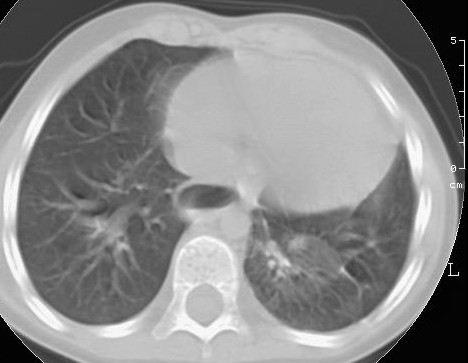

L�Rx torace eseguito in corso di uno di questi episodi aveva evidenziato la presenza di polmonite basale sinistra (Figura 1).

La TAC, eseguita a risoluzione del terzo episodio infettivo, metteva in luce la presenza di lesione malformativa, altrimenti non visibile in radiologia convenzionale (Figura 2).